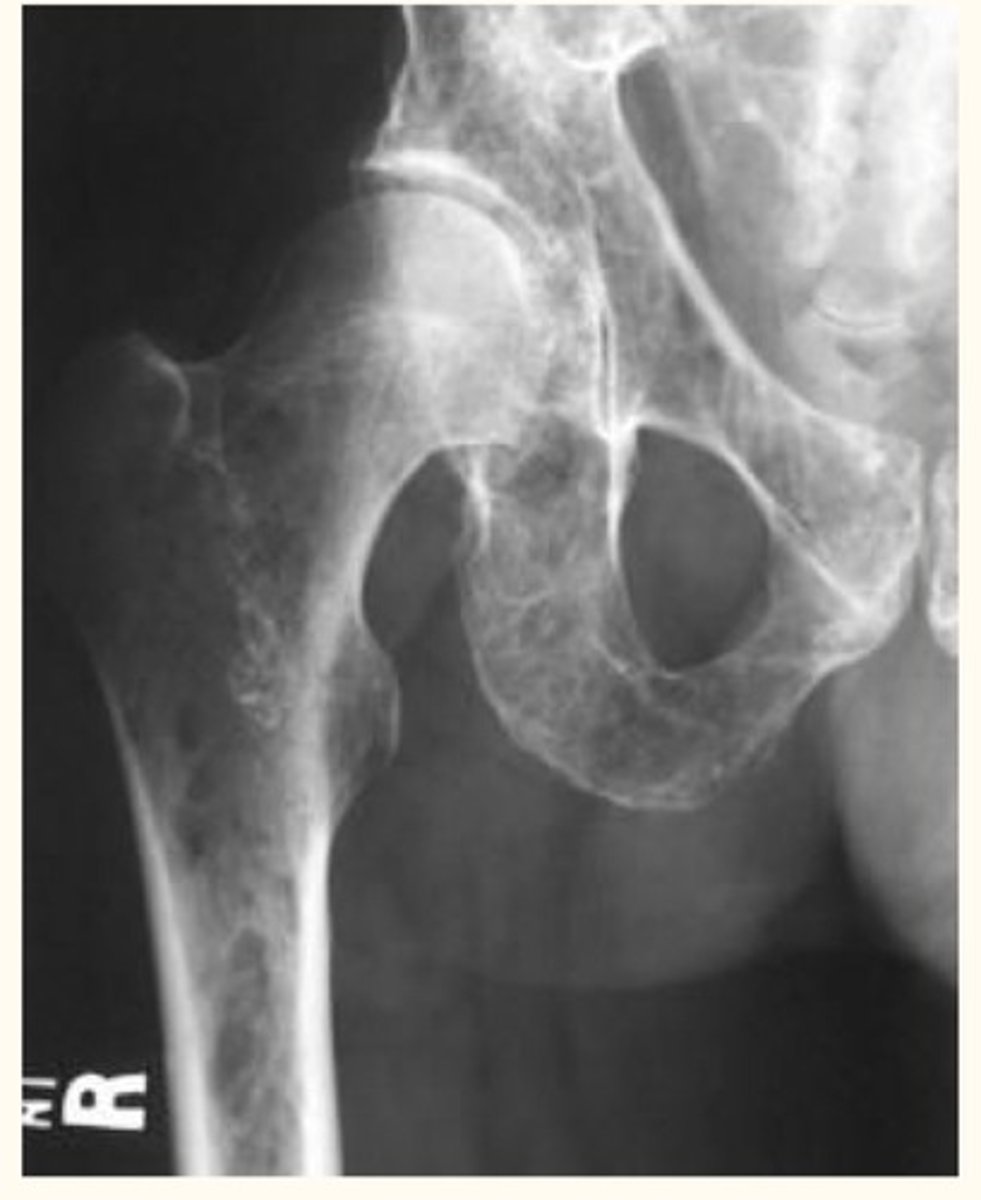

High antibody level, osteolytic lesions in bones